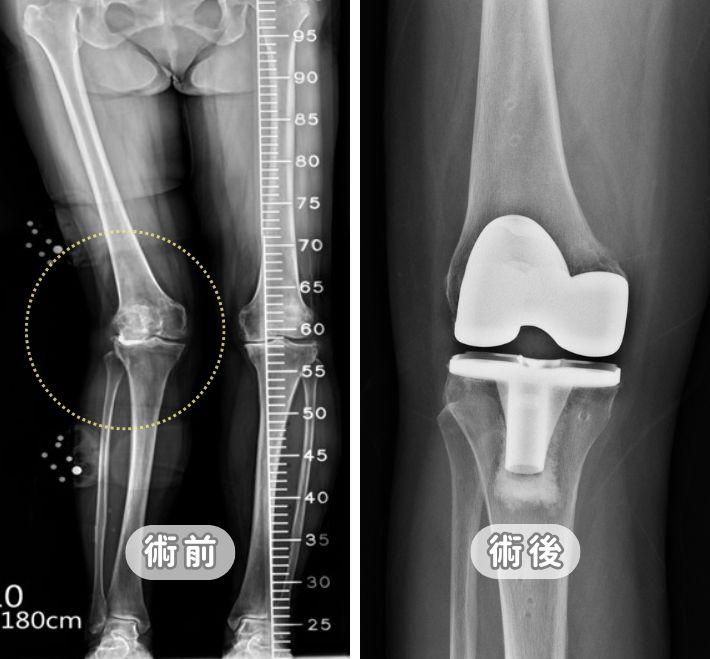

【膝關節退化】一定要換膝?免開刀治療條件與退化痛自救法

膝蓋痛一定要換關節嗎?張建鈞主任詳解膝關節退化 K-L 四階段診斷。從初期的減重、股四頭肌訓練,到 PRP 與羊膜生長因子注射,本文提供完整階梯式療法。針對重度退化,深入對比「半膝」與「全膝」置換優劣,並解析 ROSA Knee 機器人手臂如何達成 0.1 公分精準骨切除,助您術後 24 小時下床,重拾行動尊嚴。

微創膝關節置換手術全攻略:ROSA Knee 機器人手臂導航的精準醫療-退化性膝關節炎治療新方法

膝蓋痛一定要換全膝嗎?解析 ROSA Knee 3D 機器人手臂導航技術,將手術誤差降至 0.005 公分,精準平衡韌帶並保留肌肉組織。內含微創手術費用預算、ROSA 與傳統手術對照表、24小時快速康復流程,助您重拾行動自由,延長人工關節壽命。

膝蓋退化一定要換全膝?UKA半膝人工關節全攻略:置換條件與退化痛自救法

膝蓋痛一定要換全膝嗎?專業醫師解析「微創半膝人工關節置換術 (UKA)」。僅針對局部磨損修復,完整保留十字韌帶與自體骨,傷口小且術後當天即可下床。內含 UKA 與 HTO 手術對照表、術後復健與常見問題,助您精準精準找回行動力。